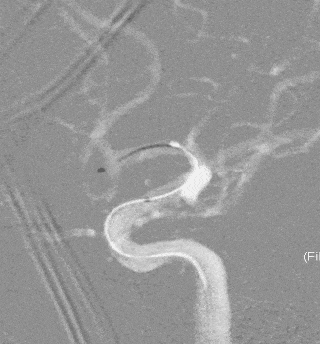

术前影像

栓塞过程

Presgo®微导丝引导支架微导管于基底动脉末端,并预留支架。陆续填塞Jasper®SS弹簧圈4枚,瘤腔填塞致密,撤出支架系统。

术后即刻影像